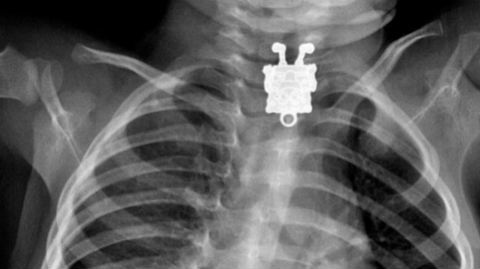

Bé trai suýt chết vì nuốt đinh dài 3cm vào bụng

Khi thấy bé trai 2 tuổi bị đau bụng và trong đồ chơi bị mất 1 cây đinh nhọn, nghi ngờ bé đã nuốt vào bụng nên gia đình đưa đi cấp cứu.